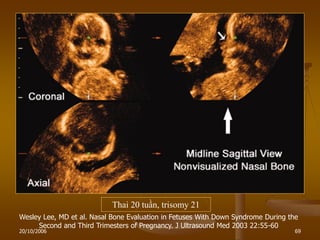

NASAL BONE

- Khảo sát trong tam cá nguyệt II.

- Thiểu sản:

+ Chiều dài xƣơng mũi < 2,5mm.

+ hoặc BPD/NB > 11.

- Ý nghĩa: Trisomy 21.

Xƣơng mũi bình thƣờng / thai 18 tuần

Bất sản xƣơng mũi: Trisomy 21

Thai 20 tuần, trisomy 21

Wesley Lee, MD et al. Nasal Bone Evaluation in Fetuses With Down Syndrome During the

Second and Third Trimesters of Pregnancy. J Ultrasound Med 2003 22:55-60